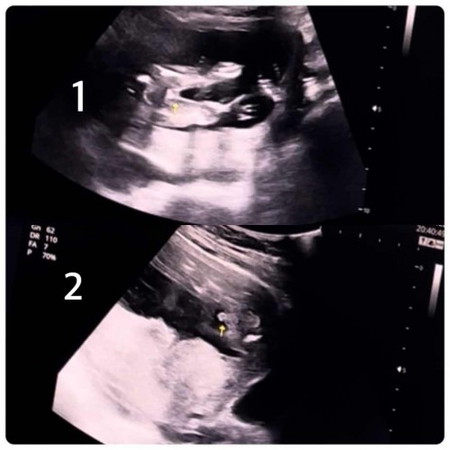

ภาพไหนคือเพศจริงๆของลูกคะ

เดือนก่อน16w+6dทีแรกคุณหมอบอกผู้หญิง(ภาพแรก)พอแปปๆคุณหมอบอกชาย(ภาพที่2)คลีนิคคนเยอะคะ หมอก็อัลฯแบบเร็วจนเราดูเวียนหัว จับจุดไม่ถูก ใครพอมีประสบการณ์คล้ายๆเราบ้างคะ

จู๋ตรงที่ลูกศรสีขาวเล็กๆชี้คะโผล่กลางหว่างขา

น่าจะผู้ชายไหมคะจู๋ชัดเชียว😊

น่าจะ ช.นะมีจู๋โผล่ออก

เหมือนจู๋ค่าาา